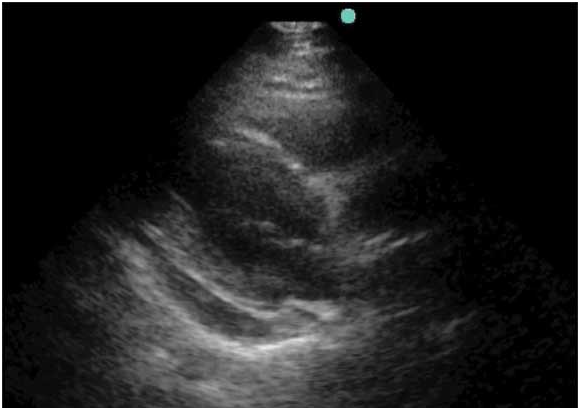

“You arrive to the emergency department for your first night shift of the month, and as you place your bag on the desk, the attending walks towards you with a chart in his hand. “Do you mind seeing this patient? It’s a COPD’er with dyspnea. It’s probably just a COPD exacerbation.” You look at the chart and see that it’s a 46 year old female with shortness of breath. As you walk into the room, you notice the patient appears slightly pale, is afebrile, has an O2 saturation of 91% and is tachycardic in the 110’s with a blood pressure of 105/76, temperature of 98.5° and respiratory rate of 26. While taking the history, you note that the patient is a smoker and recently returned from a 12 hour car ride to see relatives. Suspecting that this may be something other than simple COPD exacerbation, you grab your ultrasound machine and start with the cardiac echo (as described in the RADiUS protocol) and are able to get the following image:

This apical 4-chamber view shows severe right heart dilation, defined as a RV:LV ratio >1. However, you remember that the patient has a history of COPD, and chronic pulmonary hypertension can cause chronic right ventricular dilation1. At that moment, the patient becomes hypotensive with a systolic blood pressure in the 70’s and develops severe respiratory distress. What should we do?